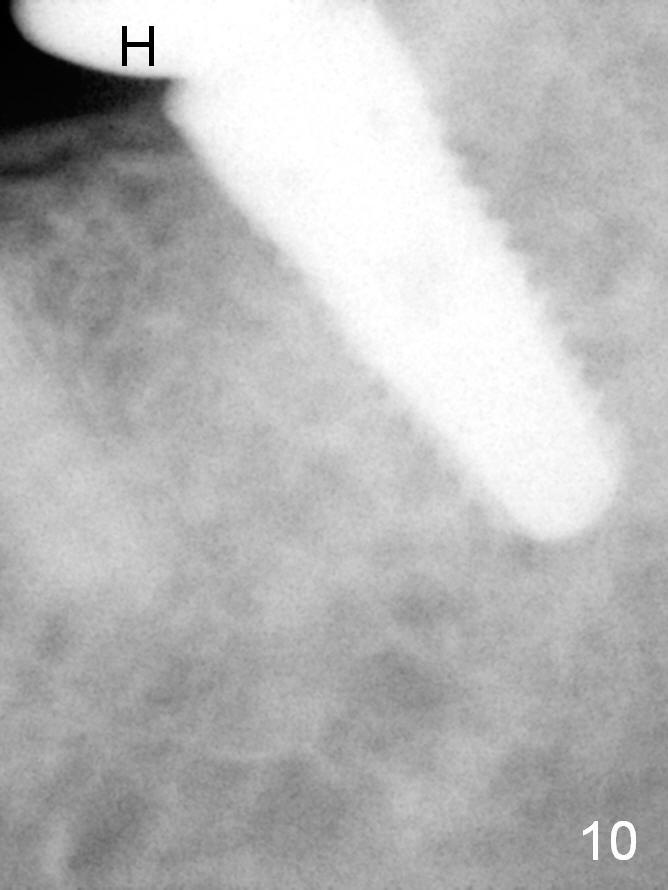

A 48-year-old lady is a dental phobic, requesting extraction of the lower left 2nd molar (Fig.1). She returns for implant placement 9 months post extraction (Fig.2). The ridge is mildly to moderately atrophic. It appears that a 5x12 mm implant is appropriate for the site (Fig.3). For safety, osteotomy is initiated at the depth of 10 mm; it appears that there is enough height for a 12 mm implant (Fig.4). The depth is controlled by drill stopper (Fig.5 S). Finally a 5x12 mm implant is apparently safely placed (Fig.6). A healing abutment is placed and the incision is sutured with 4-0 Chromic gut (Fig.7). Perio dressing is applied around the healing abutment for wound protection (Fig.8). It appears that the healing abutment (Fig.8': *) helps stabilize the perio dressing, which remains in place 1 week postop. When the perio dressing is removed, the wound around the healing abutment is healing (Fig.9). There is no bone loss around the implant 3 months postop (Fig.10 (H: healing abutment), or 16 months postop (i.e., 9 months post cementation, Fig.11,12). The patient complains of pain when she chews with the implant crown, but pain stops whenever she does not bite. Percussion does not elicit any discomfort. The gingiva is healthy. There is possibility of the buccal plate being thin or the lingual plate being perforated in the submandibular fossa. If the discomfort remains the same next 6 months, CBCT will be prescribed.